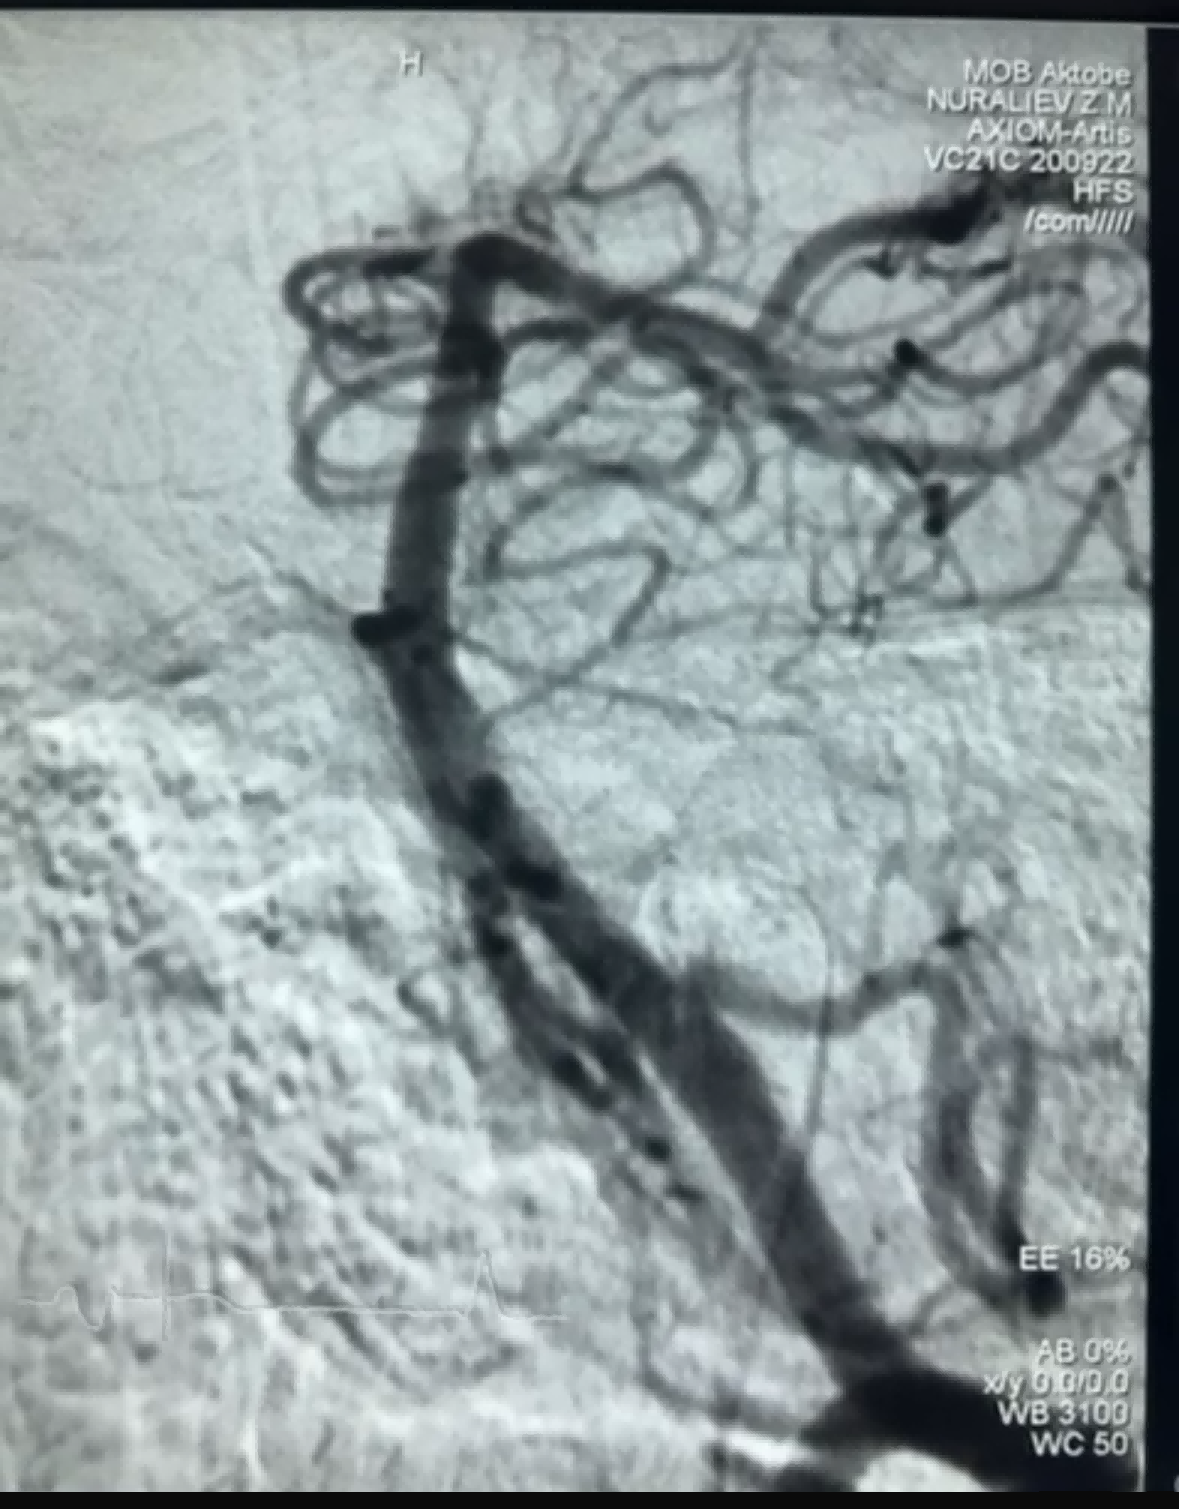

最近、ニューロセーフメディカル社のドレッジャーステントリトリーバーを使用した血栓除去術が成功した症例がありました。ドレッジャーステントリトリーバーは非侵襲性の柔らかい先端部を備えており、内膜損傷のリスクを大幅に軽減し、主に隙間の変化を挟んで血栓を捕捉する独自の特殊形状の穴設計を備えています。